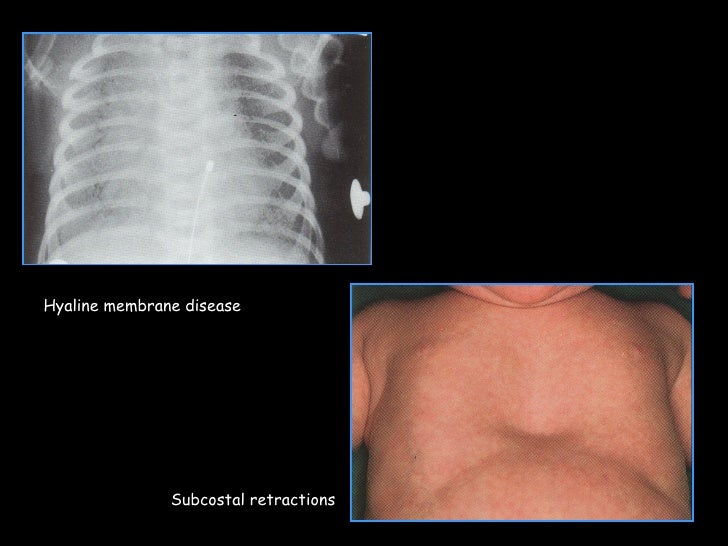

What Are Chest Retractions In Newborns . It’s easy to spot in babies and small children because their chests are softer and haven't fully. respiratory distress in the newborn is recognized as one or more signs of. neonatal respiratory distress syndrome, or rds, is a common cause of respiratory distress in a newborn, presenting. this is called a chest retraction. respiratory distress in the neonate is diagnosed when one or more of the following is present; newborns with respiratory distress commonly exhibit tachypnea with a respiratory rate of more than 60. one of the most important physical findings to be able to recognize in a newborn is the presence of retractions.

neonatal respiratory distress syndrome, or rds, is a common cause of respiratory distress in a newborn, presenting. respiratory distress in the newborn is recognized as one or more signs of. one of the most important physical findings to be able to recognize in a newborn is the presence of retractions. It’s easy to spot in babies and small children because their chests are softer and haven't fully. respiratory distress in the neonate is diagnosed when one or more of the following is present; newborns with respiratory distress commonly exhibit tachypnea with a respiratory rate of more than 60. this is called a chest retraction.

What Are Chest Retractions In Newborns newborns with respiratory distress commonly exhibit tachypnea with a respiratory rate of more than 60. neonatal respiratory distress syndrome, or rds, is a common cause of respiratory distress in a newborn, presenting. one of the most important physical findings to be able to recognize in a newborn is the presence of retractions. It’s easy to spot in babies and small children because their chests are softer and haven't fully. respiratory distress in the newborn is recognized as one or more signs of. this is called a chest retraction. newborns with respiratory distress commonly exhibit tachypnea with a respiratory rate of more than 60. respiratory distress in the neonate is diagnosed when one or more of the following is present;